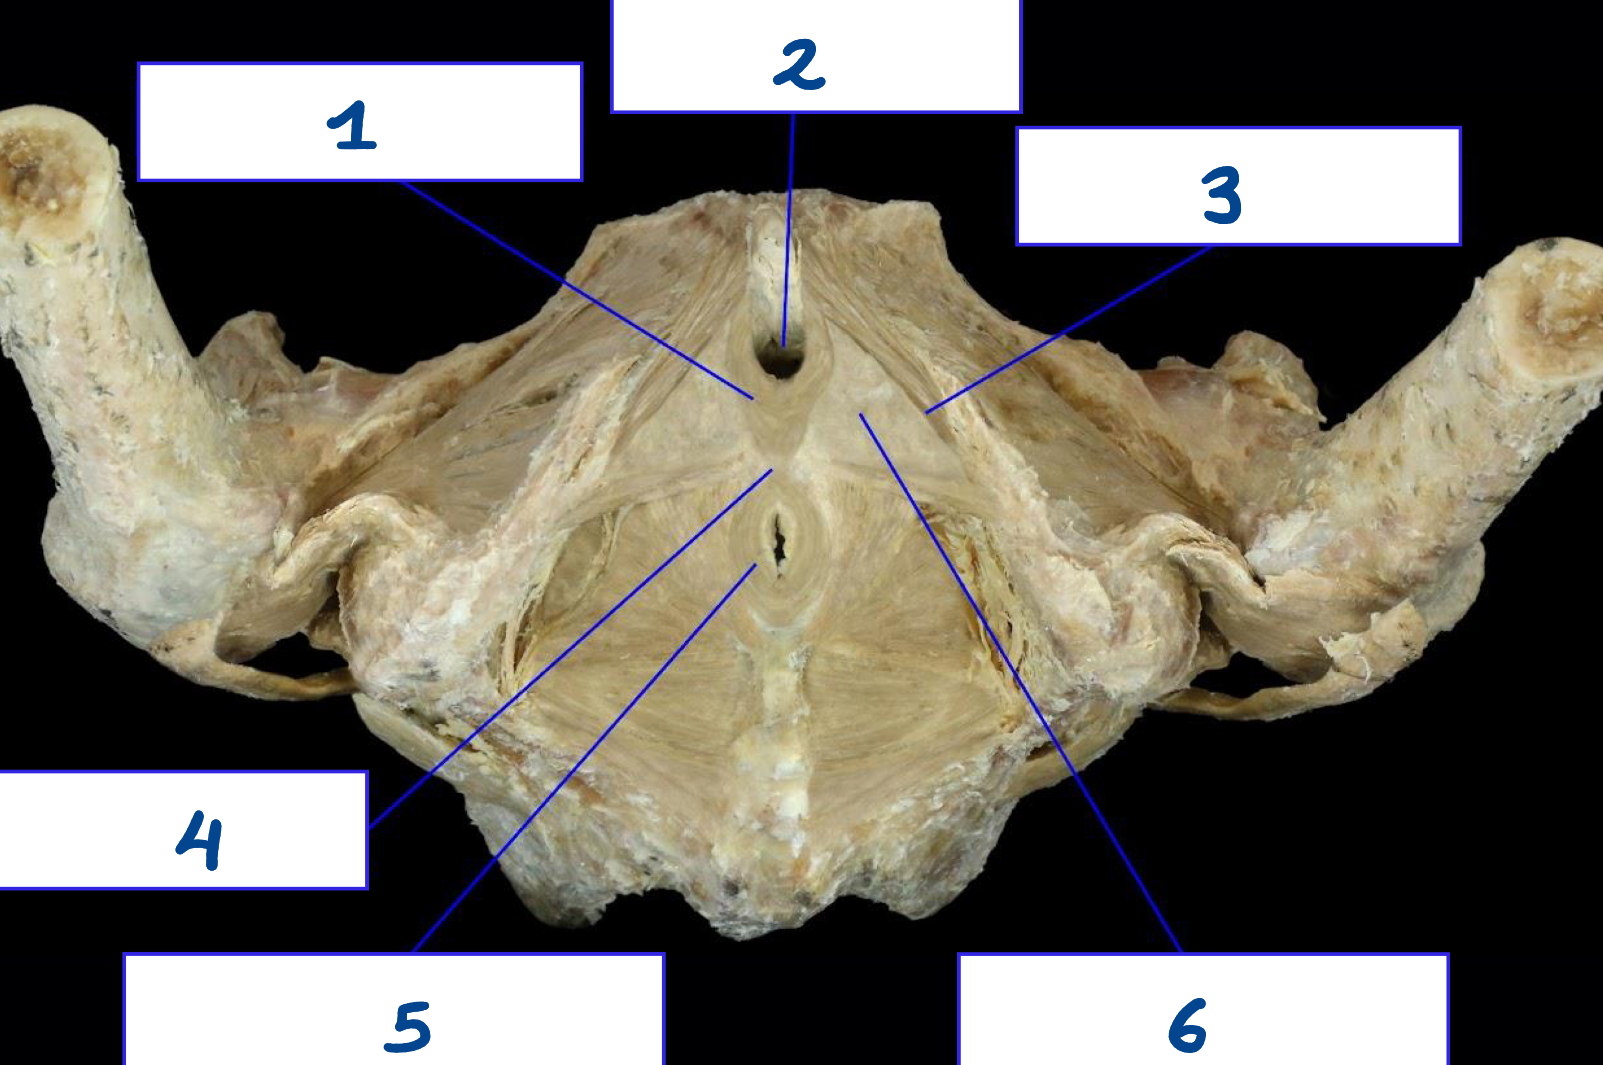

<p>What is structure 1?</p>

What is structure 1?

Sacrospinous ligament

23

New cards

<p>What is structure 2?</p>

What is structure 2?

Sacrotuberous ligament

24

<p>What is structure 3?</p>

What is structure 3?

Greater sciatic foramen

25

<p>What is structure 4?</p>

What is structure 4?

Lesser sciatic foramen